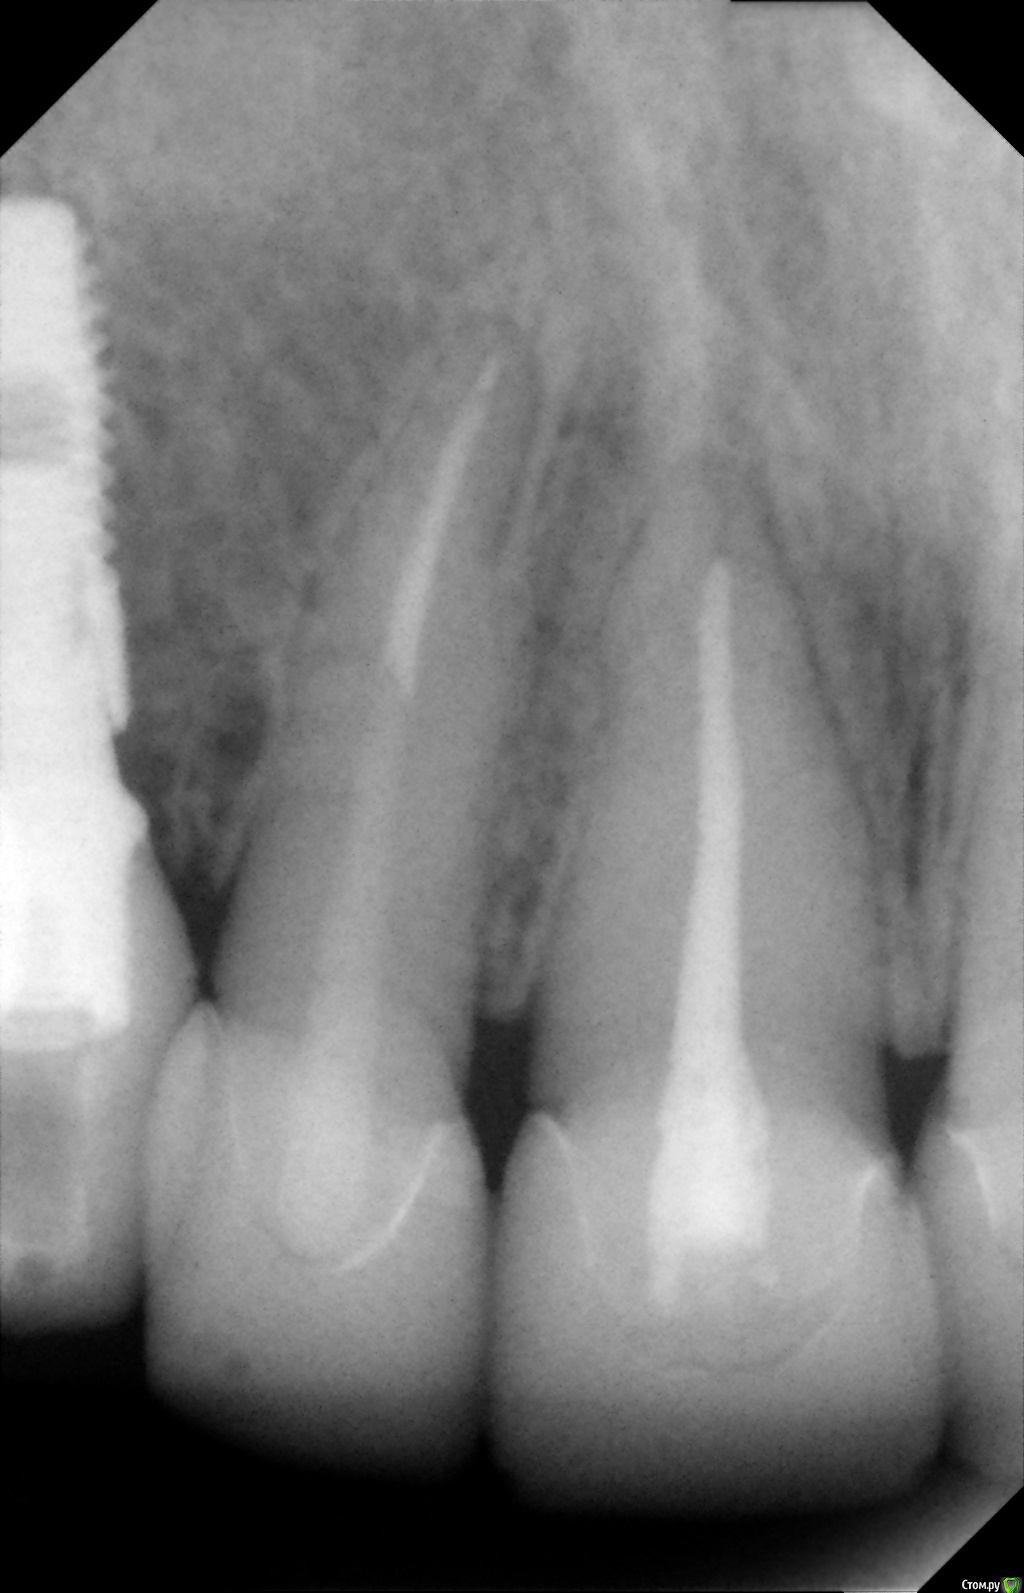

Alexandr_doc Опубликовано 21 сентября, 2018 Поделиться Опубликовано 21 сентября, 2018 Доброго всем времени! Пациентку протезировал доктор, которого уволили по ряду причин, обратилась ко мне на этапе после протезирования с жалобами на болезненность в области фронтальной группы зубов 1.2, 1.1, 2.1, 2.2, 2.3 при дотрагивании языком или пальцем. Перкуссия положительная как в вертикальном так и горизонтальном направлении. Установлены одиночные керамические коронки на каркасе из диоксида циркона. Отек, покраснение в области переходной складки отсутствует, также отсутствует болезненность при пальпации. Подвижность 1 степени. Прилагаю фотографии на этапе обращения. Ранее, на этапе протезирования было принято решение о депульпировании фронтальной группы тк присутствовала пульпитная симптоматика, после чего состояние улучшилось и остается стабильным по сей день. Предположил несколько причин оставшейся симптоматики: 1) несостоятельно проведенное эндо лечение - вариант отмел тк по прицельным снимкам и кт отсутсвуют очаги воспалительных процессов 2) некорректно изготовленные искуственные коронки ( глубокая поддесневая препаровка и агрессивный контур коронки ) 3) - окклюзионная перегрузка. Совместно с пацинеткой принято решение о снятии коронок во фронтальном отделе, была предупреждена о том, что возможно не получить хорошей динамики. С переменным успехом картина после нескольких корректировок временных коронок остается преждней. Болезненность на прежднем уровне, плюс по ходу наблюдения пришлось снять мост с опорой на уровне имплантатов, тк имели место быть воспалительные процессы в проекции имплантата 1.5. С удовольствием отвечу на все вопросы и приму любую критику. Ссылка на комментарий

Alexandr_doc Опубликовано 21 сентября, 2018 Автор Поделиться Опубликовано 21 сентября, 2018 Маргинальной гингивит. Нависающие края? Мягкий налет под коронками? Остатки цемента? Скоро будет пародонтит.Специально приложил прицельные снимки с временными коронками, где нависающие края? Цемента, лежащего тоннами там нет, думаю, что с корявыми временными коронками выкладывать пост не стал бы Ссылка на комментарий